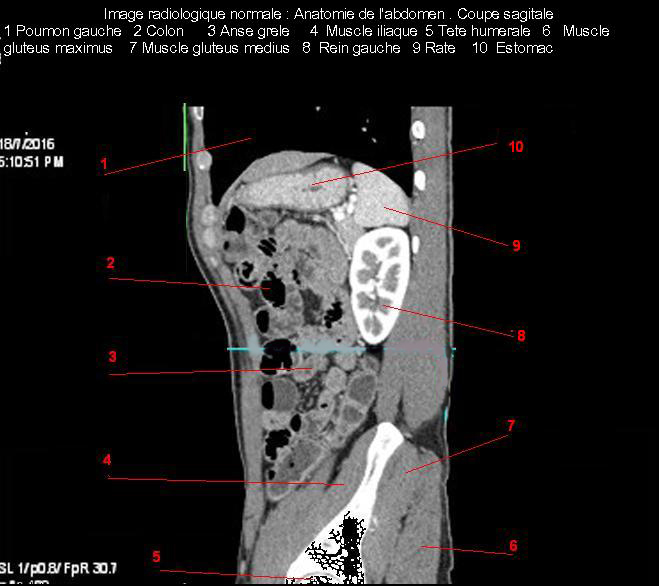

Aspect

radiologique TDM plus C+ de la rate en coupe coronal

( frontal ) . Au phase arterielle la rate rehausse

tres hyperdense |

|

Aspect radiologique TDM plus C+ de la rate en

coupe sagital